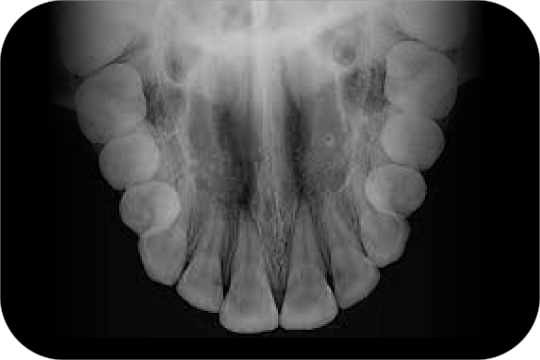

Oclusal